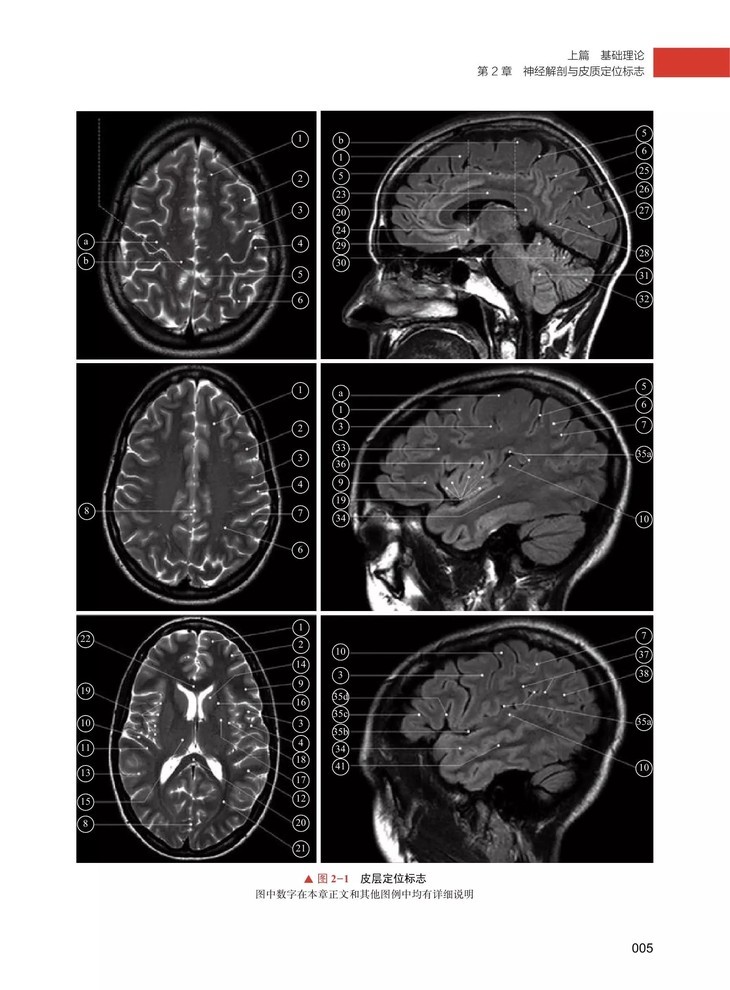

本书引进自 Springer 出版社,为全新第 3 版,提供了丰富的 fMRI 基础理论与临床实践相关知识,并详细介绍了如何克服各种成像技术问题。本书分上下两篇。上篇基础理论涵盖了神经解剖、神经电生理、fMRI 成像原理和临床常用技术,以及数据分析方法等内容;下篇临床应用则主要介绍了 fMRI 应用于儿童所涉及的问题、fMRI 技术与经颅磁刺激及脑电刺激的结合、fMRI 在癫痫诊疗的应用、fMRI 辅助术前定位、多发硬化和海马的功能解剖与图像分割,以及 fMRI 应用于神经退行性疾病等内容。随着 fMRI 相关技术的不断发展,除应用于基础脑研究外,也逐渐应用于临床诊断,尤其是术前定位方面。本书理论与实践并重,有助于读者快速学习掌握fMRI 技术,适合神经影像学医师、神经内科学医师及神经外科学医师、医学生参考阅读。